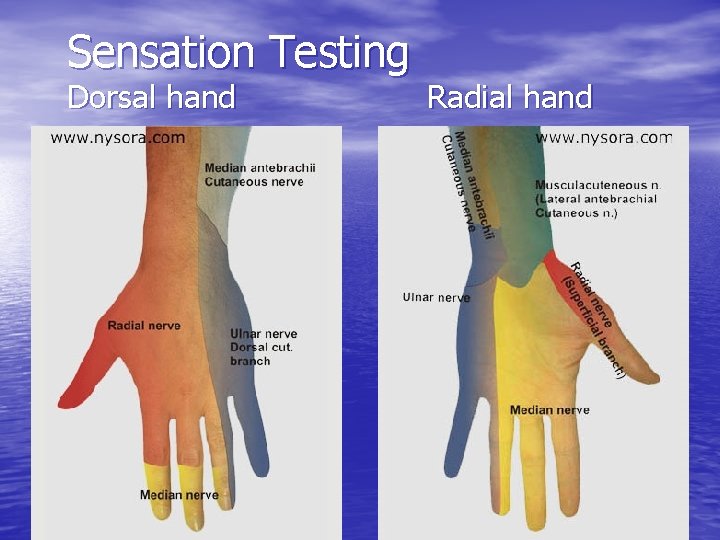

Sensation Testing Dorsal hand Radial hand

NEUROLOGIC EXAM Sensation Testing • Neurological Level – Dermatomes- 3 neurologic levels – C 6, C 7, C 8